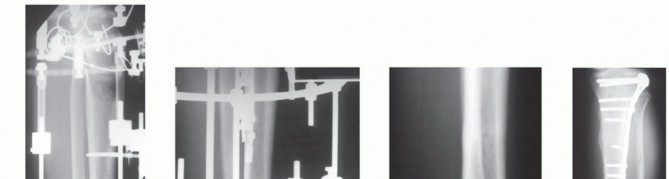

A delayed shortening is then carried out until the arthrodesis is compressed (FIG 5). The patient is encouraged to mobilize the forefoot and toes and knee.

FIG 5 • A. Lateral x-ray of bifocal external fixator. The proximal tibia has been lengthened between the ⅝-full ring block and the double-ring block on the midtibia. B. Lateral x-ray of the tibiocalcaneal arthrodesis with compression between the midtibia and the footplate. The foot is in plantar neutral alignment. C. Mature tibiocalcaneal arthrodesis with the plafond fused to the calcaneus and navicular. D. AP x-ray with axial alignment of arthrodesis. The patient had a valgus deformity after frame removal of the transport. The tibia was realigned with a lateral locked plate.

The force applied to the leg is gradually increased with mature healing of the bone transport and arthrodesis observed at 1 year after fixator removal (FIG 5C,D*).

The patient self-selects walking and training shoes that have cushioned heels with a rounded radius heel.

An alternative is to place a locked plate spanning the transport on the medial or lateral tibial shaft (FIG 5D).